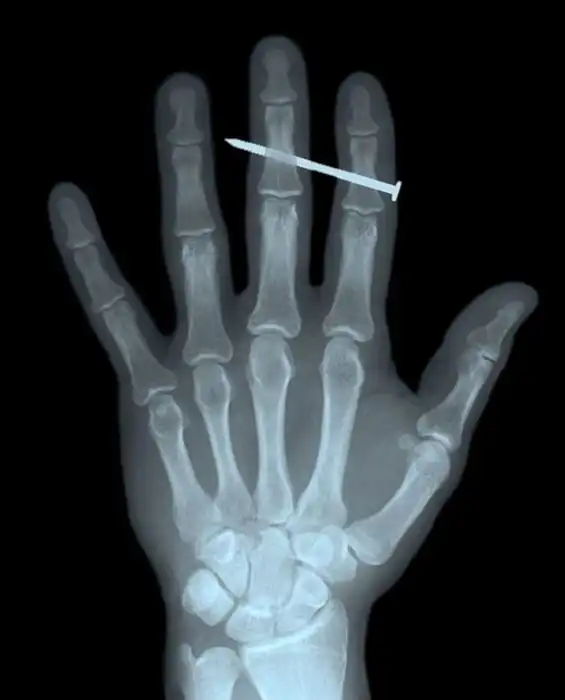

Жуткие рентгеновские снимки

Порой даже не верится, с какими странными и необычными повреждениями в травматологию могут поступить пострадавшие. Всю эпичность профессии врачей травматологии могут с легкостью подтвердить рентгеновские снимки.